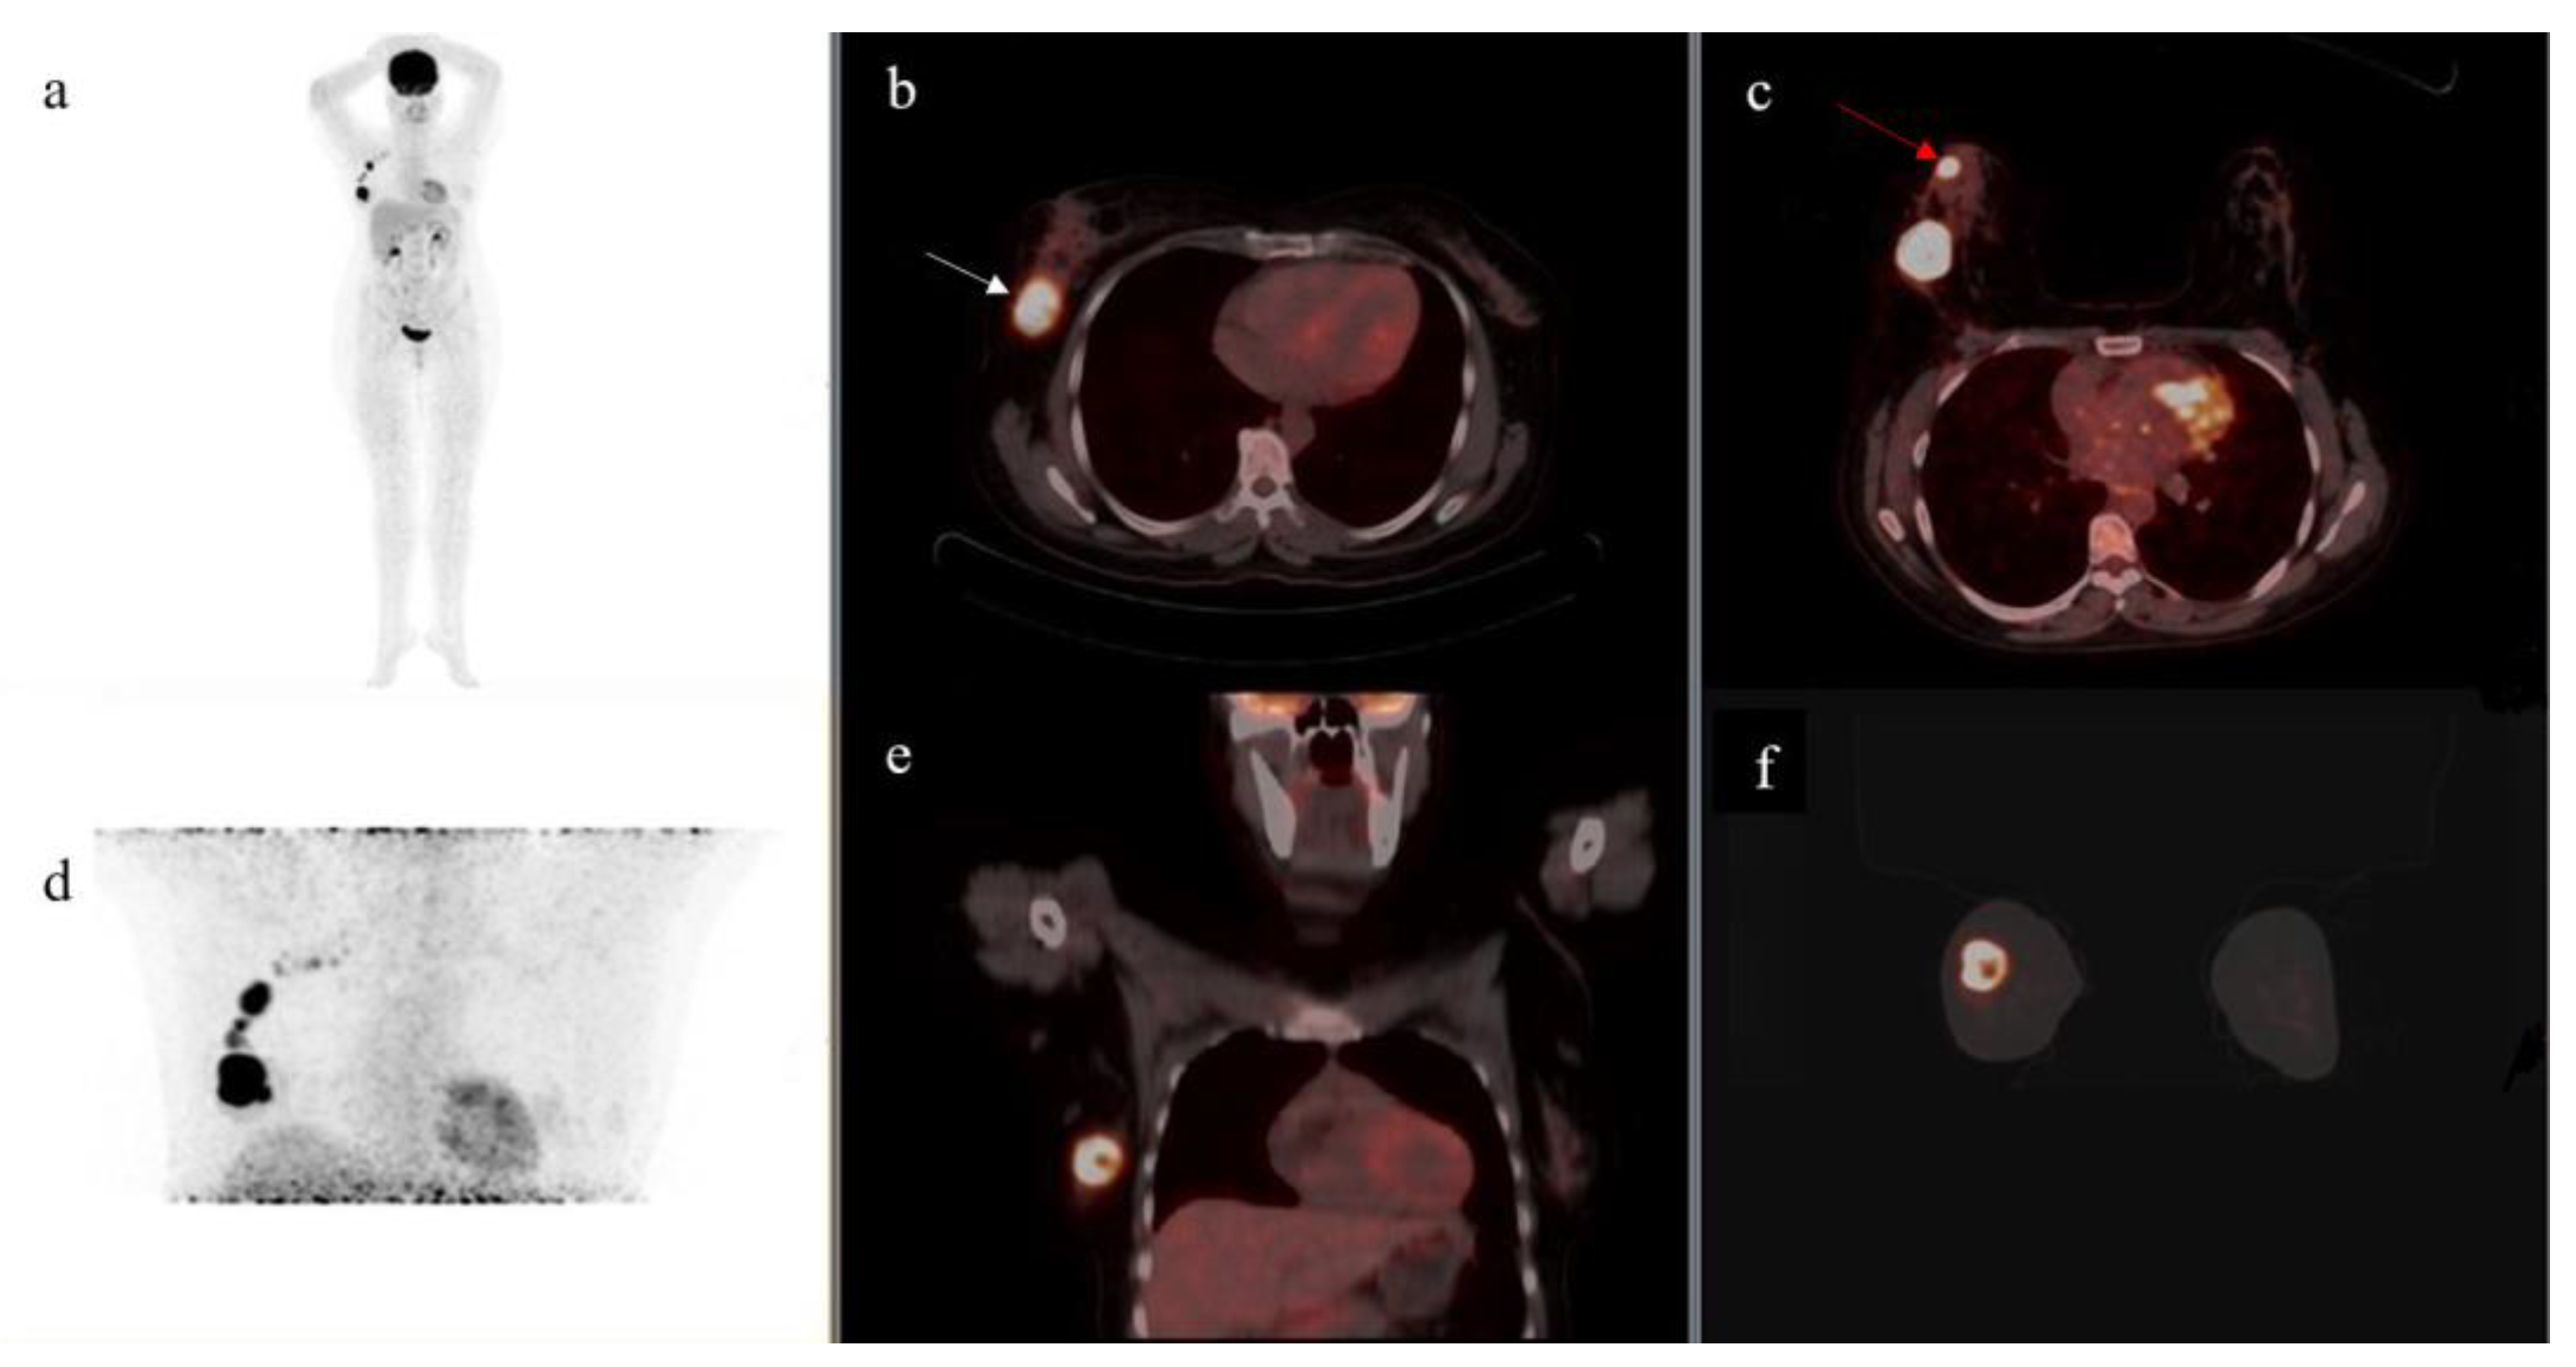

- On supine position acquisition, primary breast lesions were missed in three patients, all of which were detected on prone position. One such example is seen in Figure 2,

- A single lesion was detected on supine position in two patients who, on prone position, each had two lesions detected (Table 1),

- One lesion was detected on supine position in a patient who was found to have three lesions on prone acquisition (Table 1).